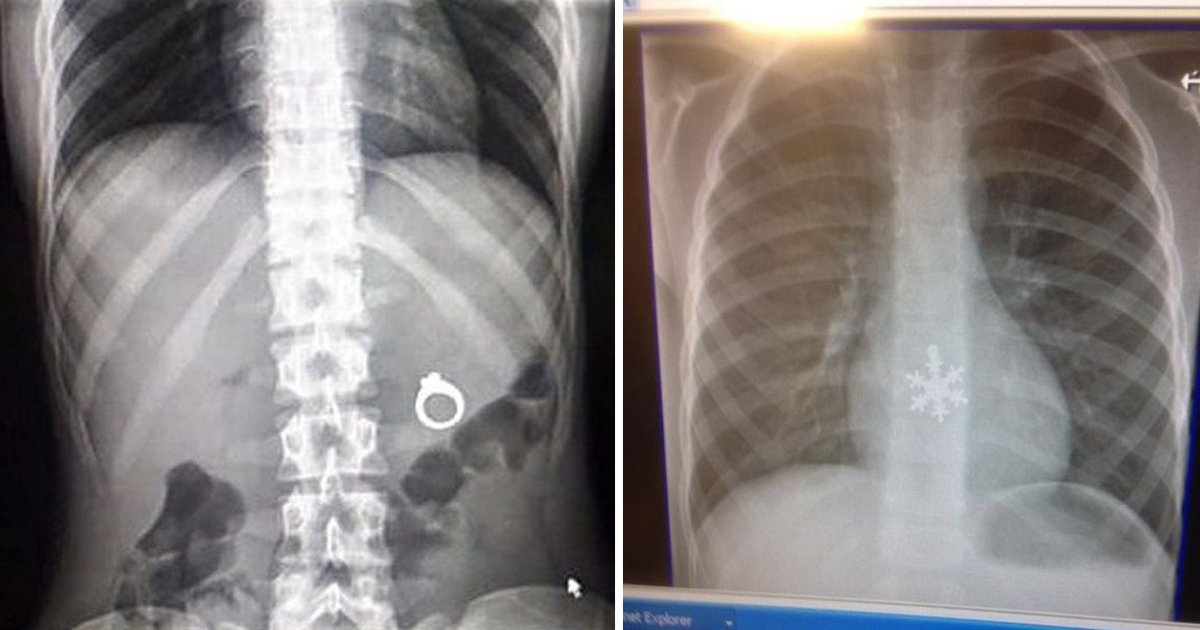

O raio X é uma das grandes invenções da humanidade e é muito útil em algumas situações. Crianças e animais, por exemplo, vivem engolindo objetos pequenos pois não têm noção do que fazem, e nesses casos o raio X é bastante utilizado.

Os radiologistas estão tão acostumados a ver coisas estranhas em imagens de raios X, que talvez nem se surpreendam com as imagens abaixo, mas com certeza você se surpreenderá.

6 – Uma aliança perdida